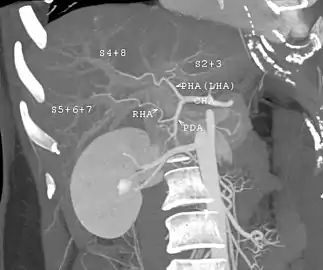

Couinaud classification system

Shape of human liver in animation, with eight Couinaud segments labelled

In the widely used Couinaud system, the functional lobes are further divided into a total of eight subsegments based on a transverse plane through the bifurcation of the main portal vein.[28] The caudate lobe is a separate structure that receives blood flow from both the right- and left-sided vascular branches.[29][30] The Couinaud classification divides the liver into eight functionally independent liver segments. Each segment has its own vascular inflow, outflow and biliary drainage. In the centre of each segment are branches of the portal vein, hepatic artery, and bile duct. In the periphery of each segment is vascular outflow through the hepatic veins.[31] The classification system uses the vascular supply in the liver to separate the functional units (numbered I to VIII) with unit 1, the caudate lobe, receiving its supply from both the right and the left branches of the portal vein. It contains one or more hepatic veins which drain directly into the inferior vena cava.[28] The remainder of the units (II to VIII) are numbered in a clockwise fashion:[31]